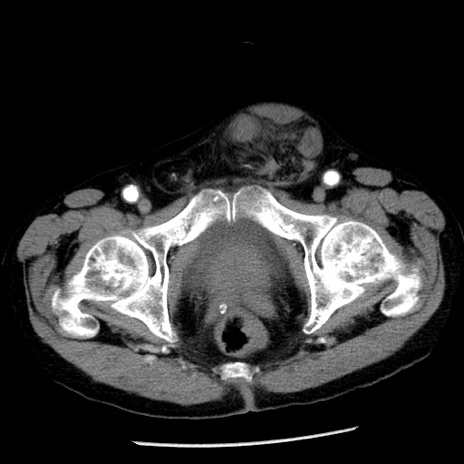

冠状断像

【症例】80歳代男性

【主訴】嘔吐

【現病歴】昨晩2回嘔吐あり、今朝になっても嘔吐あり。来院。

【既往歴】胃潰瘍

【身体所見】意識清明、BT 37.6℃、BP 166/95mmHg、HR 100bpm、SpO2 97%、腹部:平坦・軟、腸蠕動音聴取良好、圧痛なし。

【データ】WBC 21900、CRP 1.46